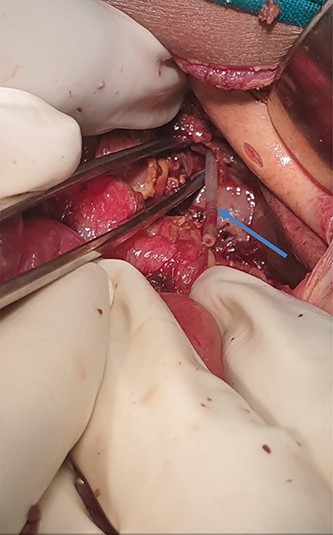

Necrosis of 20 cm of the jejunum extending cephalad to involve the duodenum, stomach and abdominal part of the esophagus was noted with extensive autolysis from abdominal esophagus to the ligamentum treitz (Fig. 2).

Necrosis of the jejunum and whole length of duodenum with detached mesentery.